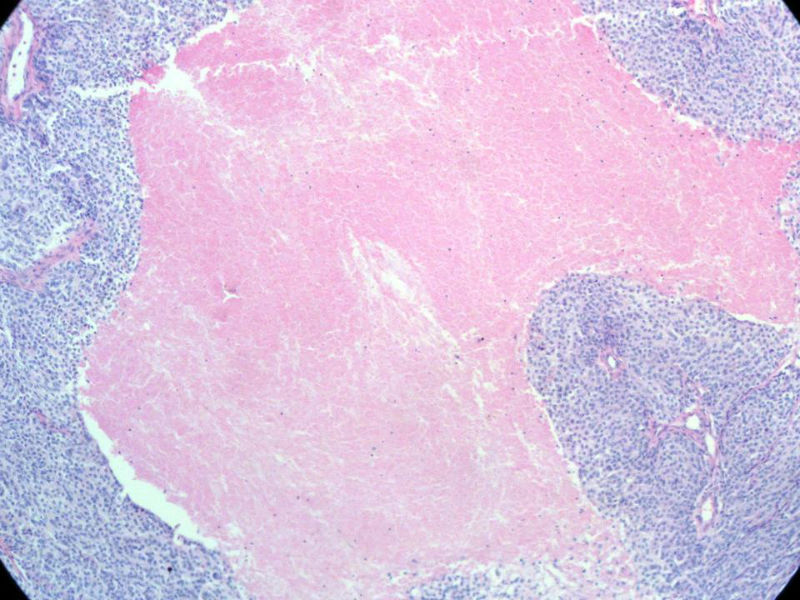

女,64岁,头晕半月,CT检查颅内左颞叶占位,侵犯颅骨和颞肌,手术切除肿物。肉眼,灰白色结节状肿物,3X3X2厘米,边界不清,切面灰黄色,质软。

特别提示:手术前曾做过介入肿瘤栓塞。镜下核分裂15/HP。脑左颞部占位图1

梭形细胞与上皮样漩涡状结构,富于细胞,见个别沙砾体,并见肿瘤性坏死。颅骨及其横纹肌等软组织内见肿瘤呈侵袭性生长。但细胞异型性不是很大。鉴别:

1)恶性脑膜瘤

2)非典型性脑膜瘤

由于非典型性脑膜瘤也可以发生地图状坏死,甚至侵袭性生长。需要计数核分裂数/10HPF,以资鉴别诊断。